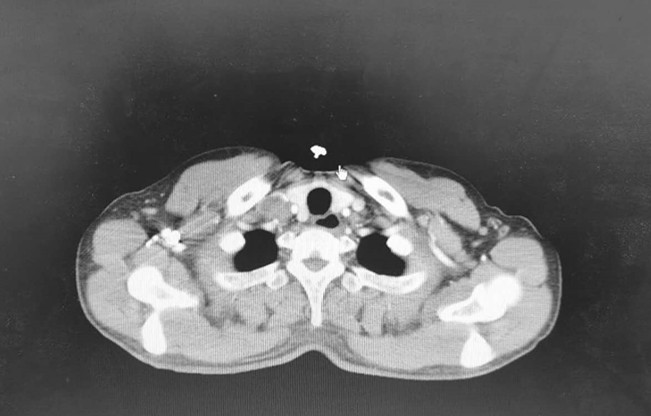

5月8日CT结果

2020年5月8日:疗效评价PR。